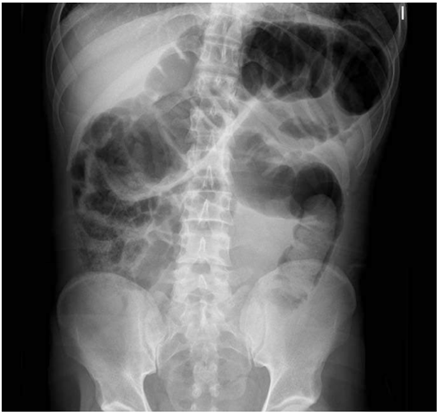

Varón de 39 años, natural de Marruecos, sin antecedentes de interés, que acude a urgencias por cuadro clínico de 15 días de dolor abdominal, asociado a vómitos intermitentes, deposiciones diarreicas y rectorragia, con empeoramiento progresivo hasta presentar obstrucción intestinal de 48 horas de evolución. La radiografía abdominal mostró dilatación marcada del colon (figura 1), que se corroboró con la TC abdominal (figura 2), donde además se visualizó una extensa invaginación a nivel del colon sigmoides, sin clara lesión subyacente, condicionando una oclusión mecánica con distensión retrógrada (ciego de 8 cm de diámetro con válvula competente). No se identificaron neumoperitoneo ni otros signos de perforación.